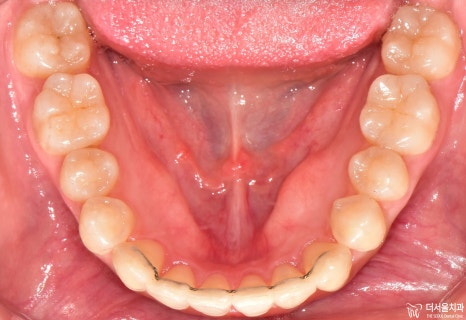

먼저 교합면에서 보게 되면, 앞니들의 총생이 관찰됩니다.

정면에서는 뭔가…. 그렇게 고르지 않은 치열이라는게 느껴지죠?

어색한 느낌이 계속 듭니다.

측면에서는 확연히, 돌출입 형태를 확인하실 수 있습니다. 이렇게 앞니들이 앞으로 뻐드러져

있는데 심미선을 기준 으로 봤을 때 입술의 위치가 그대로 예쁜 곳에 있는 걸 보면

연조직이 얇아서 가능하다라는 것을 추측할 수 있겠네요.

아울러, 이 분의 경우에는 비발치 교정 으로 치료를 하길 원하셨었습니다.